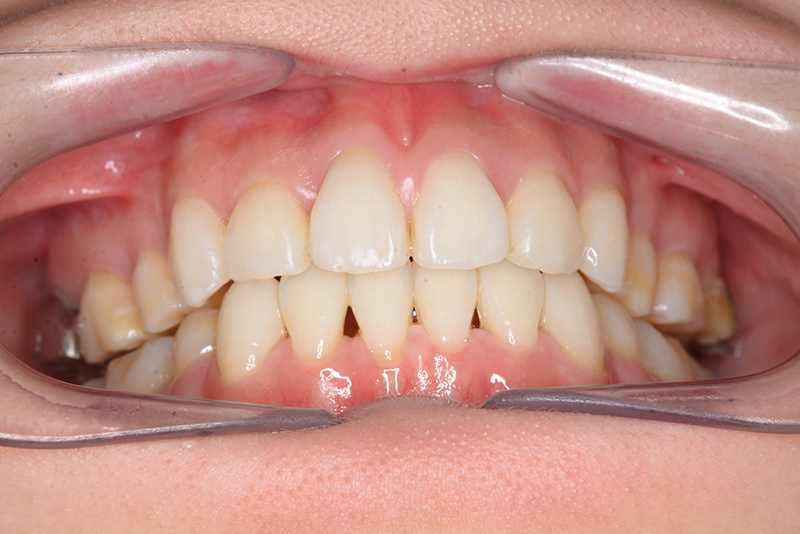

初診時

FP・IOP

顔貌所見 正貌はほぼ左右対称。側貌はconvex type、Nasolabial Angleは小さく口唇は突出しており、閉唇時には口唇閉鎖不全が顕著に認められた。

口腔内所見 over jet 4.0mm、over bite 2.0mm、臼歯関係Ⅰ級、犬歯関係Ⅱ級で上顎前歯は唇側傾斜を呈しており、上下顎前突の様相を呈していた。